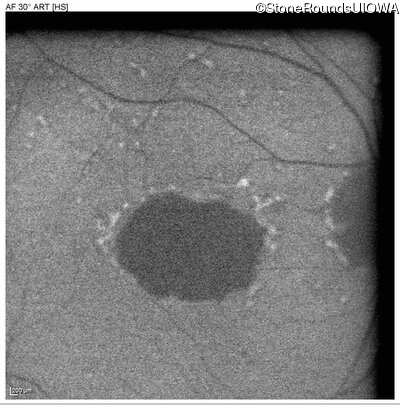

Pattern Dystrophy (IIC)

Age at visit: 47 years

This 47 year man first experienced some decrease in his central vision about 10 years ago.

Diagnosis & molecular findings

Disease Gene Allele 1 variant(s) Allele 2 variant(s) Inheritance mode

Pattern Dystrophy PRPH2 Gly167Asp GGC>GAC   AD